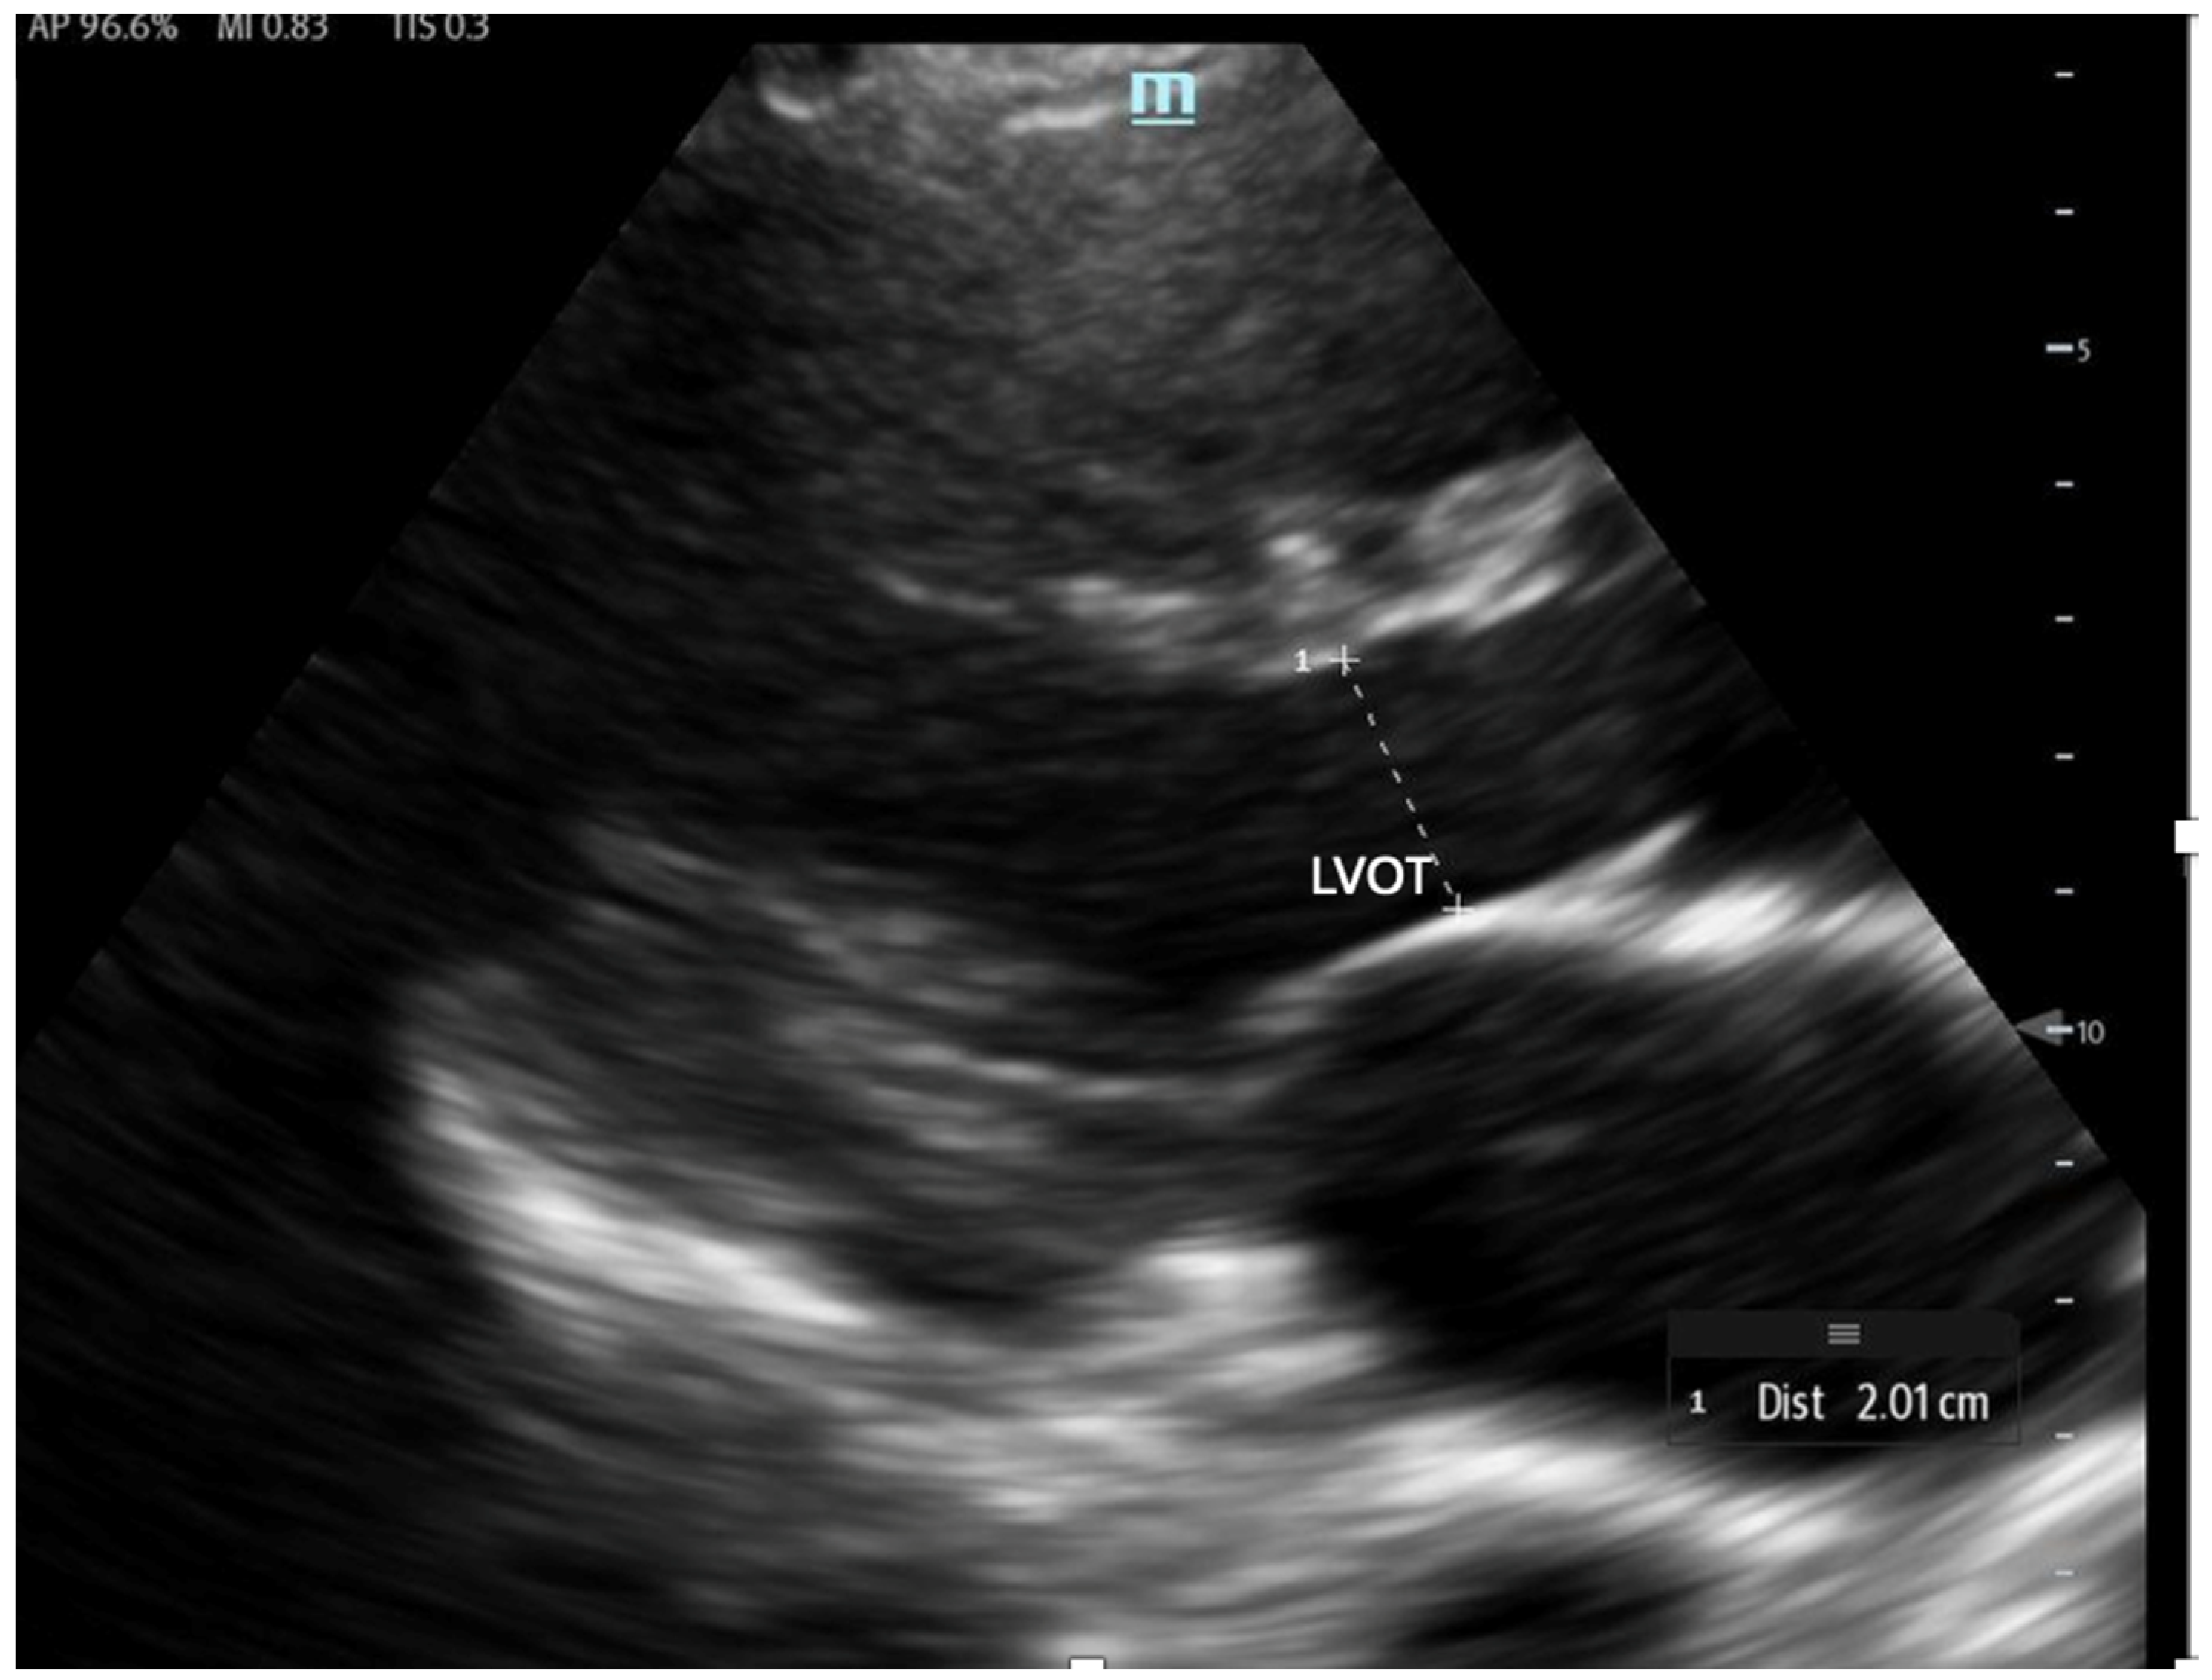

To estimate SV and CO, ultrasound requires two key measurements: the LVOT diameter and the LVOT-VTI. Cardiac output can also be indexed to body surface area to calculate the cardiac index (CI), further enhancing the hemodynamic assessment.

The LVOT diameter is measured in the PLAX view, focusing on the LVOT and aortic valve when maximally open during mid-systole (Figure 12). The measurement is taken at the base of the aortic valve, and the area is calculated using the formula:

Figure 12.

The LVOT diameter measured below the opening of the aortic valve in a zoomed-in parasternal long axis to be incorporated into the LVOT area formula.

The VTI is measured in the apical five-chamber view using pulse-wave Doppler, with the sample volume placed at the center of the LVOT to trace the velocity curve (Figure 13). The VTI, measured in centimeters and averaged over several beats to account for beat-to-beat variability, reflects the distance that blood is propelled forward from the LVOT to the aorta with each contraction. When used in conjunction with blood pressure and lactate levels, the LVOT-VTI can help guide shock etiology as well. A low VTI with hypotension and elevated lactate suggests low-output shock (e.g., cardiogenic), and a high VTI with hypotension and elevated lactate may suggest distributive shock (e.g., early sepsis). The normal range is between 17 and 23 cm, and it serves as a surrogate for stroke volume. When used in conjunction with the clinical picture, the VTI can also serve as a valuable tool for longitudinal assessment and is shown to decrease total time on vasoactive agents [61].